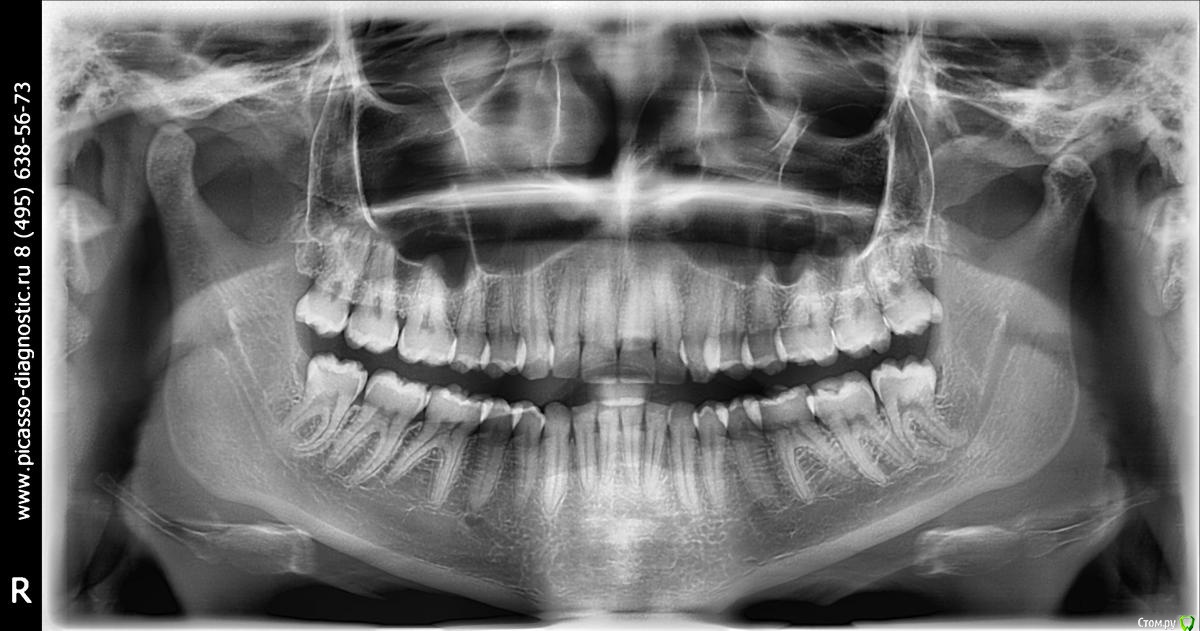

Elena_Mnzh Опубликовано 19 ноября, 2016 Поделиться Опубликовано 19 ноября, 2016 (изменено) 23 года, дистальный прикус,зубы ровные, визуально всё нормально,но челюсть неприятно выпирает. план лечения: удаление н.8ок и верхних 4ок, установка брекетов. Подскажите, пожалуйста, необходимо ли удаления? Я сама понимаю и вижу, что вроде да, но окружение запугивает байками про расхождение зубов или западющий прикус. И второй вопрос:насколько серьёзная проблема? Помогут ли брекеты или есть смысл в хирургическом лечении? И, последнее, какие негативные последствия, если я оставлю прикус в таком же состоянии?Заранее большое спасибо за ответы! Изменено 19 ноября, 2016 пользователем Elena_Mnzh Ссылка на комментарий

Yana guapa Опубликовано 23 ноября, 2016 Поделиться Опубликовано 23 ноября, 2016 23 года, дистальный прикус,зубы ровные, визуально всё нормально,но челюсть неприятно выпирает. план лечения: удаление н.8ок и верхних 4ок, установка брекетов.Подскажите, пожалуйста, необходимо ли удаления? Я сама понимаю и вижу, что вроде да, но окружение запугивает байками про расхождение зубов или западющий прикус. И второй вопрос:насколько серьёзная проблема? Помогут ли брекеты или есть смысл в хирургическом лечении? И, последнее, какие негативные последствия, если я оставлю прикус в таком же состоянии?Заранее большое спасибо за ответы!все планы лечения имеют право быть. в каждом из них есть свои плюсы и минусы. выбирать только вам.при удалении верхних четверок профиль у вас еще сильнее ухудшится (не обижайтесь, просто у вас сейчас нижняя челюсть стоит кзади, а потом еще и верхняя губа уйдет. это никак не вписывается в каноны современной красоты с пухлыми губками и тд))) )если НЕ удалять четверки, то свою верхнюю челюсть вы оставляете как есть (только наклон резцов поправить надо), а нижнюю челюсть надо будет поставить в правильное положение. Уж каким способ это будете делать решать вам и вашему врачу (перемещение с помощью брекетов и пружин или хирургия). все взвешивается, рассчитывается и принимается решение.п.с. 8-ки удаляйте, даже если лечится на брекетах не будете (уж очень они у вас высоко в отличии от других зубов прорезались, страдает сустав) Ссылка на комментарий